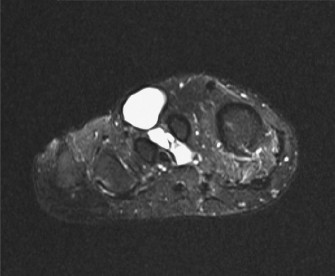

- Magnetic Resonance Imaging (MRI): The gold standard for local staging. It provides detailed information on tumor size, exact anatomical location, relationship to neurovascular bundles, bone, joints, and adjacent soft tissue compartments. T1-weighted, T2-weighted with fat suppression, and post-contrast T1-weighted sequences are typically utilized. MRI helps delineate the extent of peritumoral edema and identify skip lesions.

Figure 1: Pre-operative MRI depicting a soft tissue mass in the foot/ankle, illustrating its anatomical relationship to surrounding structures. High-resolution imaging is crucial for accurate staging and surgical planning in clear cell sarcoma. -